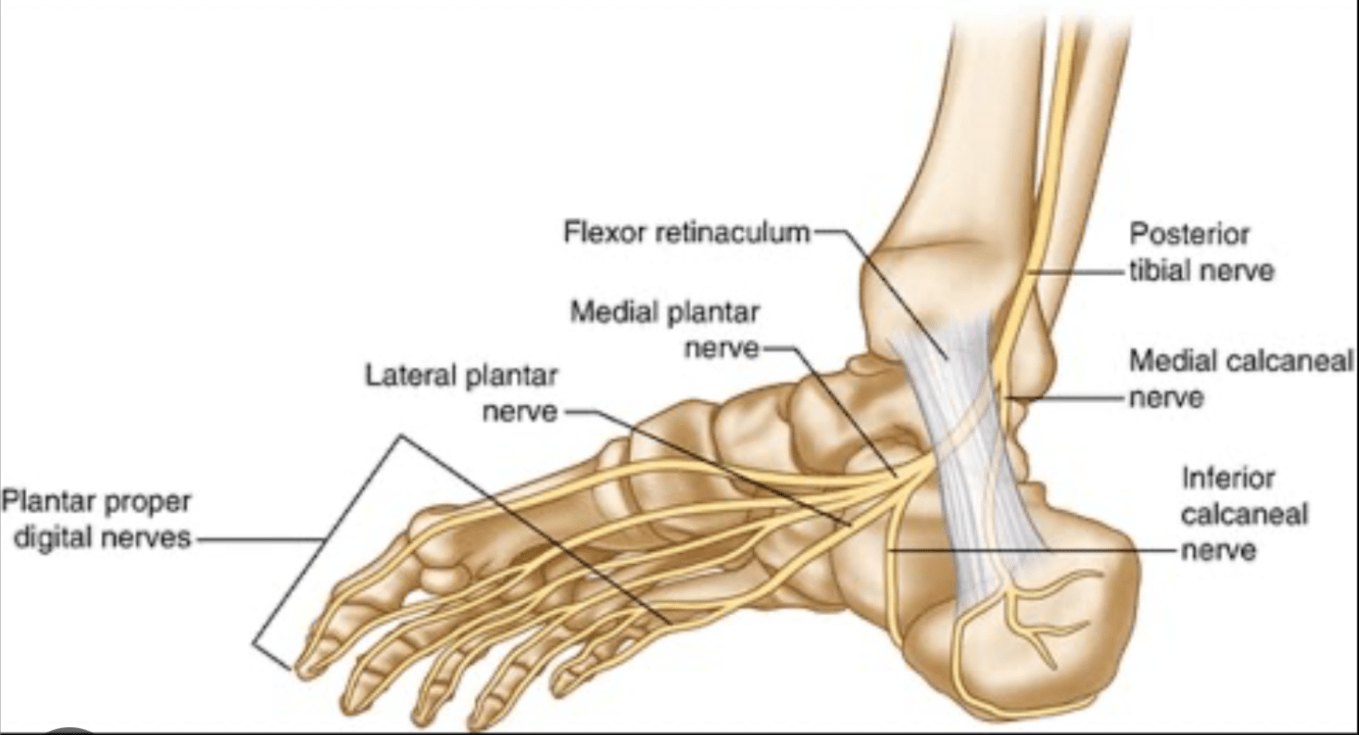

Name the occluded sensory nerves of the plantar foot.